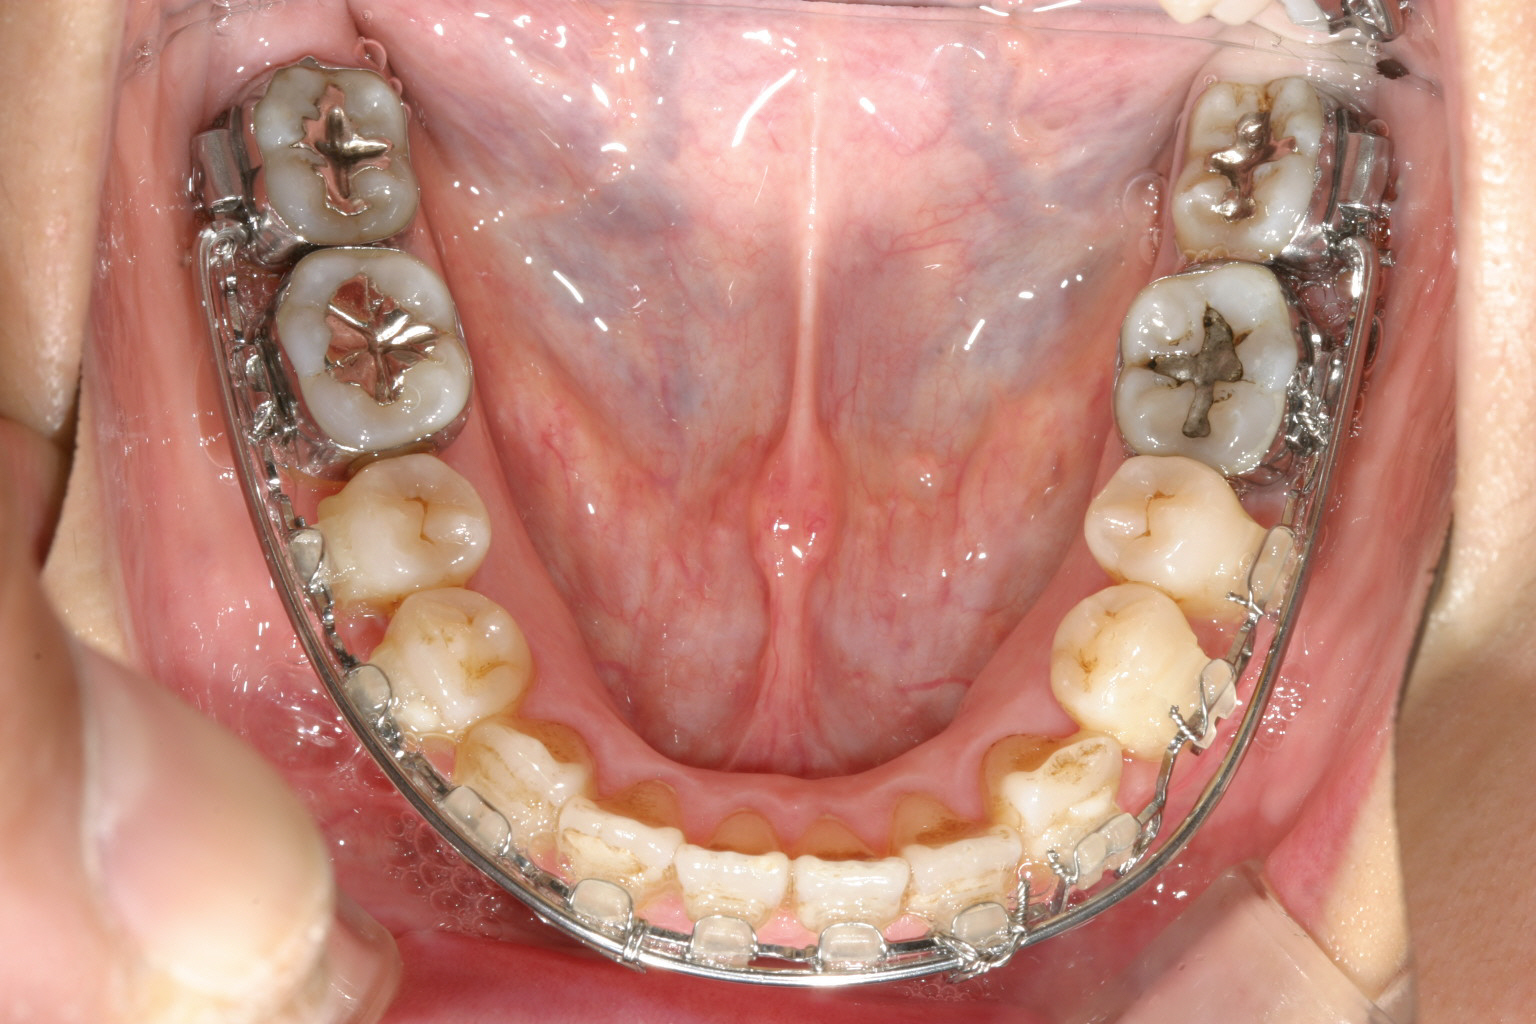

下顎もマルチループの外側に太いマリガンワイヤーが入っています、この太いワイヤーのお陰で内方に倒れていた臼歯が立ってきました。

下顎も申し分有りません。

下顎臼歯が内方傾斜している為咬合高径が下がり顎関節症を発症していました。

そこでアーチをU字にするのと同時に傾斜していた歯を直立させ、またマルチループワイヤーで咬合高径を挙げました。

そうする事により顎関節にゆとりが出来関節音も消えました。